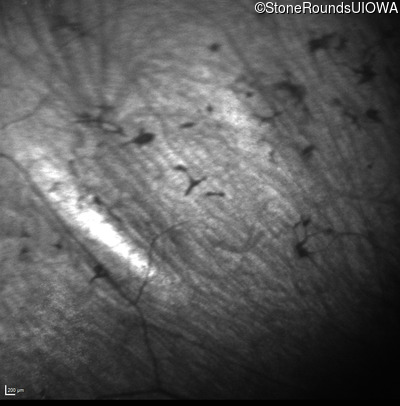

Infrared Fundus Photograph - Left - No Light Perception

Exemplar